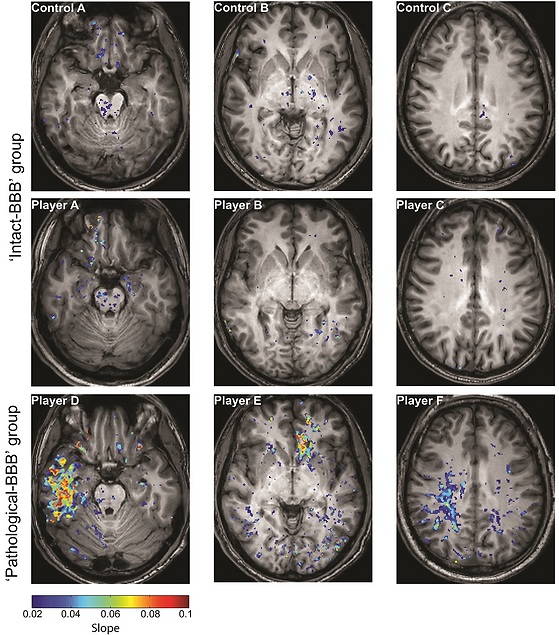

The new method of MRI detects and localizes pathologies in the brain's blood vessels caused by even mild brain injuries. The Dynamic Contrast-Enhanced MRI generates more detailed brain maps that are able to show brain regions with vascular abnormalities.

"We tested it in football players from a local team and used athletes in non-contact sports as a control group," Friedman said. "The big difference is that 40 percent of the football players showed significant pathology (in the blood vessels and blood barrier) before any other pathology can be seen," he said.

The damage only showed up in the MRI Friedman and his team developed. The same players who showed brain damage in the contrast-enhanced MRI showed completely normal brain scans in previous MRI exams.